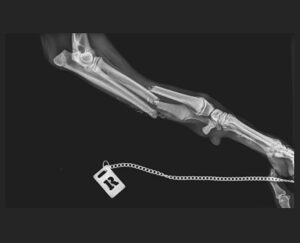

Mit dem Preisgeld möchten wir dieses Mal ganz konkret Simbad helfen. Simbad ist ein junger Galgorüde und wurde von einem Auto angefahren. Er musste notoperiert werden. Diagnose: beidseitiger Ellen- und Speichenbruch der Vorderläufe. Unsere spanischen Tierschutzkollegen, der Protectora in Villena, kümmern sich aufopferungsvoll um Simbad, obwohl das Geld schon an allen Ecken und Kanten fehlt. Übrigens: Simbad sucht noch ein liebevolles Zuhause.